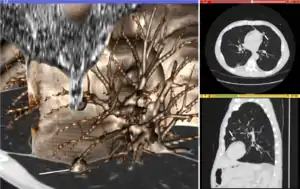

Visualization

Visualization plays several key roles in Medical Image Computing. Methods from scientific visualization are used to understand and communicate about medical images, which are inherently spatial-temporal. Data visualization and data analysis are used on unstructured data forms, for example when evaluating statistical measures derived during algorithmic processing. Direct interaction with data, a key feature of the visualization process, is used to perform visual queries about data, annotate images, guide segmentation and registration processes, and control the visual representation of data (by controlling lighting rendering properties and viewing parameters). Visualization is used both for initial exploration and for conveying intermediate and final results of analyses.

The figure "Visualization of Medical Imaging" illustrates several types of visualization: 1. the display of cross-sections as gray scale images; 2. reformatted views of gray scale images (the sagittal view in this example has a different orientation than the original direction of the image acquisition; and 3. A 3D volume rendering of the same data. The nodular lesion is clearly visible in the different presentations and has been annotated with a white line.